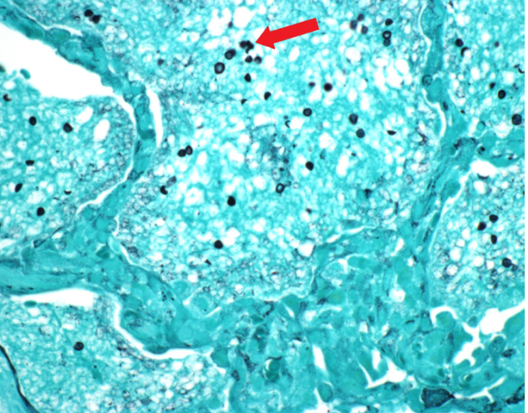

Alcohol Hepatitis

Hepatic steatosis is a nonspecific condition characterized by triglyceride accumulation within the hepatocellular cytoplasm. The pathogenesis of alcohol-induced hepatic steatosis appears related primarily to a decrease in free fatty acid oxidation secondary to excess NADH production by the 2 major alcohol metabolism enzymes, alcohol dehydrogenase and aldehyde dehydrogenase. Contributing pathogenetic factors include impaired lipoprotein assembly and secretion and an increase in peripheral fat catabolism. As seen in the image, fatty tissue that is routinely fixed will microscopically demonstrate cytoplasmic vacuoles as the lipid is dissolved during histologic processing. In frozen sections, lipids can be demonstrated by staining with oil red O or Sudan black.